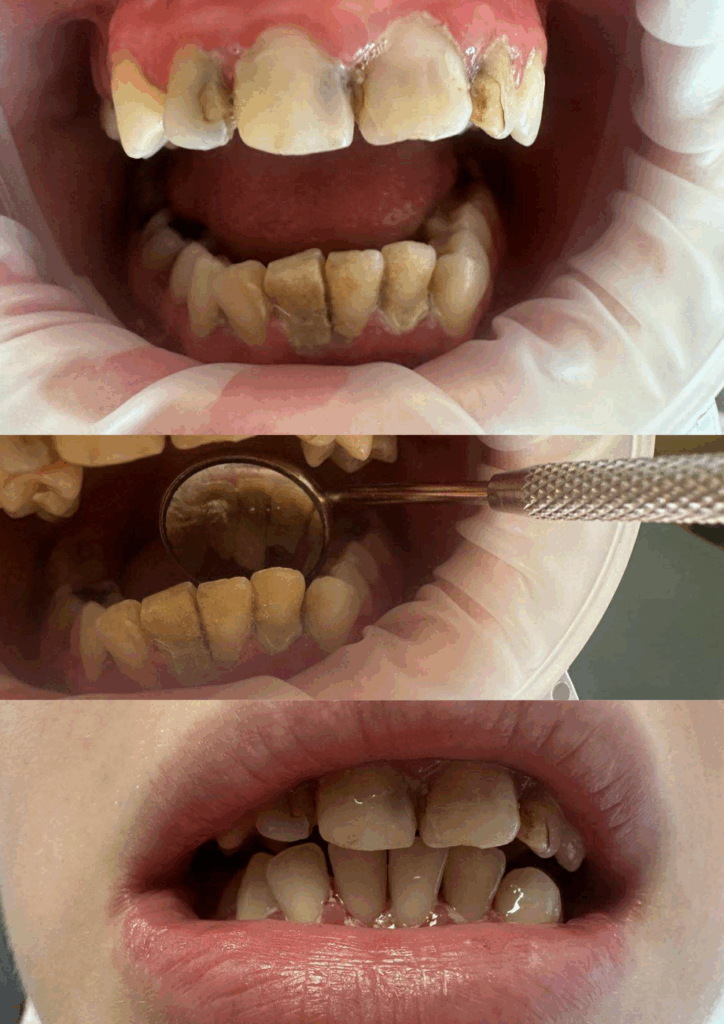

Usuwanie kamienia nazębnego i osadów

Higienizacja jamy ustnej – przed i po zabiegu

Efekt po skalingu

Higienizacja jamy ustnej – efekt przed i po

Usuwanie retajnera wraz z higienizacją jamy ustnej